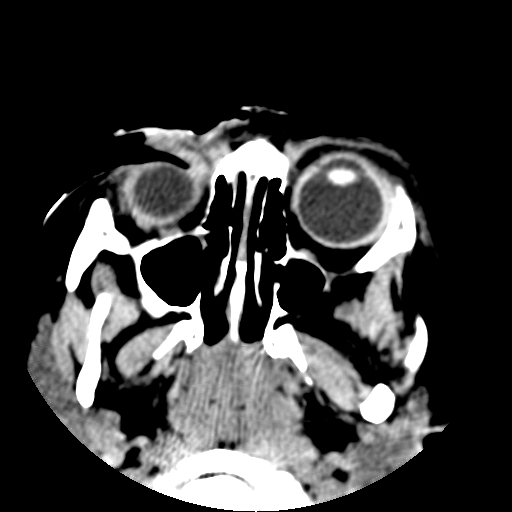

以下是引用深泽交通医院在2009-10-16 8:25:00的发言:[br]右眼环出血伴异物

以下是引用卜一在2009-10-16 15:01:00的发言:[br]右眼球挫裂伤伴异物!

以下是引用拾荒者在2009-10-17 18:38:00的发言:[br]鼻面部皮下积气,右侧睑缘及眼球壁高密度异物影,左侧眼球壁晶状体内侧缘处是圆形低密度影。低密度异物?应提请眼科医生注意。